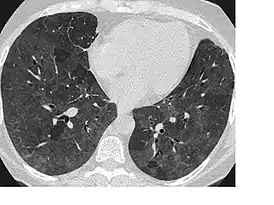

Симптом «матового стекла»

Симпто́м «ма́тового стекла́» — неспецифический радиологический симптом, отражающий различные патологические изменения в лёгочной ткани на уровне альвеол. Визуализируется при компьютерной томографии как туманное, матовое снижение прозрачности лёгочной ткани с дифференцируемым рисунком сосудов и бронхов на этом фоне. Данный симптом может быть обусловлен частичным снижением воздушности лёгочных альвеол (транссудативной, экссудативной или иной природы), их частичным спадением (гиповентиляцией) или утолщением их стенок. Так как данный симптом неспецифичен, необходимо иметь в виду анамнестические данные, клиническую картину и сопутствующую патологию. В связи с известной субъективностью оценки наличия симптома «матового стекла», следует учитывать параметры сканирования и визуализации; так, слишком узкое лёгочное окно создаёт «пятнистость» изображения, искажающую истинную картину, а низкое разрешение и большая толщина срезов (более 4 мм) создают эффект усреднения, скрадывающий и размывающий мелкие детали.

Пациент с экзогенным аллергическим альвеолитом. Обширные зоны снижения воздушности лёгочной ткани по типу «матового стекла», на фоне которых определяются «воздушные ловушки». | |

Пневмонии и пневмониты любой этиологии (бактериальной, вирусной, грибковой и т. д.) являются одной из наиболее распространённых причин фокального или диффузного симптома «матового стекла», который может отражать либо неполное заполнение просвета альвеол содержимым (при начальных или остаточных воспалительных проявлениях), либо инфильтрацию альвеолярных стенок (внутридолькового интерстиция). Фокальные участки снижения воздушности альвеол по типу «матового стекла» при бактериальной пневмонии более типичны на фоне иммунодефицита, реже — у иммунокомпетентных пациентов[1]. Паттерн диффузного или диффузно-мозаичного «матового стекла», не сопровождающийся какими-либо иными изменениями, может свидетельствовать о пневмоцистной пневмонии. Цитомегаловирусная пневмония также может проявляться лишь этим паттерном, но может дополняться расширением бронхов и утолщением их стенок, участками консолидации, часто присутствует плевральный выпот. Наряду с инфекционными пневмонитами, симптом диффузного «матового стекла» сопровождает и различные варианты неинфекционного поражения внутридолькового интерстиция — идиопатические интерстициальные пневмонии, экзогенный аллергический альвеолит и др.